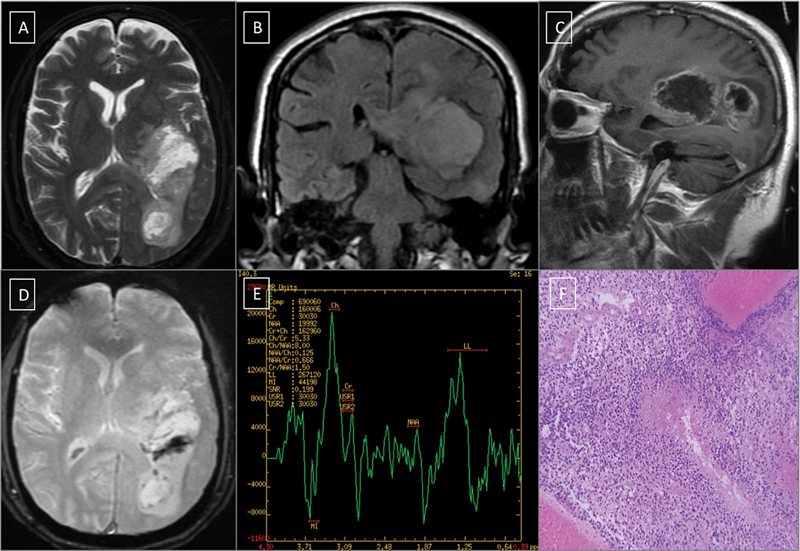

Objective  Gliomas are a devastating and heterogeneous group of primary brain tumors. Previously, the source of glioma was undetermined. Recent literature indicates that neural stem cells, or progenitors, are proposed to be the source of glioma. The prognosis of different types of gliomas differs due to their various biological tissue types. Besides the histological grade, the two useful immunohistochemistry markers that show the tumor's biological behavior are isocitrate dehydrogenase (IDH) labeling and the K i -67 labeling index. We sought to determine the magnetic resonance imaging (MRI) characteristics associated with IDH mutational status and ascertain whether MRI combined with IDH mutational status, can better predict the clinical outcomes of gliomas. Materials and Methods  This period study was conducted in the Department of Radiology, Sri Ramachandra Institute of Higher Education and Research, Chennai, Tamil Nadu, India for 5 years (May 2016-May 2021). The study cohort included 30 patients diagnosed with gliomas who underwent preoperative MRI followed by surgical resection and histopathological examination. Preoperative MRI images were done to assess qualitative tumor characteristics such as location, margin of tumor, extent, cortical involvement, cystic component, mineralization or hemorrhage, and contrast enhancement. Discussion  Differences in MRI features between IDH-mutant (MT) and IDH-wild-type (WT) groups were analyzed using the chi-square test for categorical variables and the Mann-Whitney U test for continuous variables. Statistical analysis was conducted using SPSS software. Results  Among the 30 patients evaluated, 18 had IDH-WT and 12 had IDH-MT type gliomas. Male predominance (73.33%) was noted in our study. Brainstem location, indistinct borders (83.33%), less cortical involvement (72.22%), less cystic changes (88.89%), more area of necrotic component (44.44%), significantly increased choline/creatine (Cho/Cr) ratio, and choline/N-acetyl aspartate (Cho/NAA) ratio favors IDH-WT tumors. Positive T2-fluid-attenuated inversion recovery mismatch sign is more frequently seen in IDH-MT (7/12; 58.33%) tumors than in IDH-WT (4/18; 22.22%) tumors. Whereas well-defined contours (66.67%), more cortical involvement (83.33%), more cystic changes (58.33%), and less area of necrotic component favor IDH-MT type tumors. Conclusion  MRI is a very promising and valuable tool for differentiating among glioma subtypes and predicting tumor-proliferative behavior in glioma cases. The combination of MRI characteristics with IDH mutation status enhances the predictive accuracy for clinical outcomes in glioma patients. This approach could potentially guide treatment planning and improve prognostic assessments.